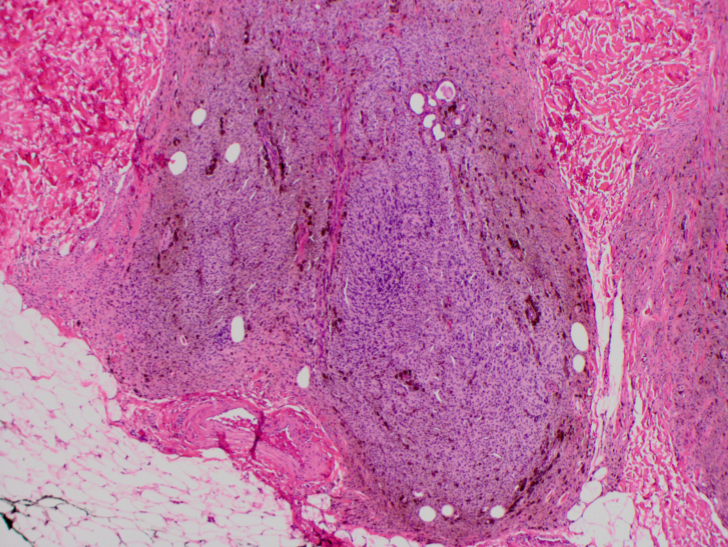

Rosai Dorfman

Fibrotic nodules showing light and dark areas

Sheets of histiocytes (light areas) with nodules of lymphoytes (dark areas)

Emperipolesis (intact cells, especially lymphocytes and plasma cells, passing through histiocytes)

S100 positive, CD1a negative, CD68 positive